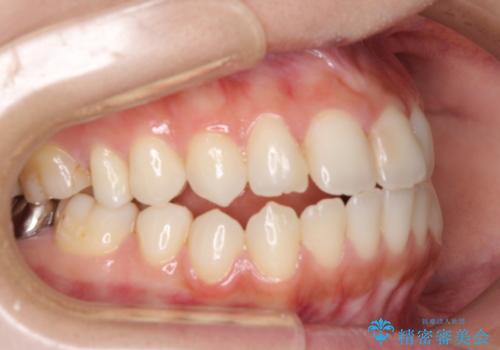

オープンバイトによる見た目を治したい インビザラインでの矯正治療

- オープンバイトのため、話しているときの見た目が気になるとのことで来院された患者様です。

下顎骨は左側にシフトしており、咬み合ったときには奥歯と前歯の一部しか接触していない状態でした。

骨格的な左右差は歯列矯正は改善できないため、上下歯列が全体的に接触することをゴールとしてインビザラインにて矯正治療を行うこととしました。

前歯のデコボコの解消と並行して上下の奥歯を圧下させるようにすることで、前歯を接触させるように計画しました。

上下の隙間に舌が入り込むことがオープンバイトの原因であったため、舌の筋肉のトレーニングも並行して行い、後戻りの抑制を図りました。